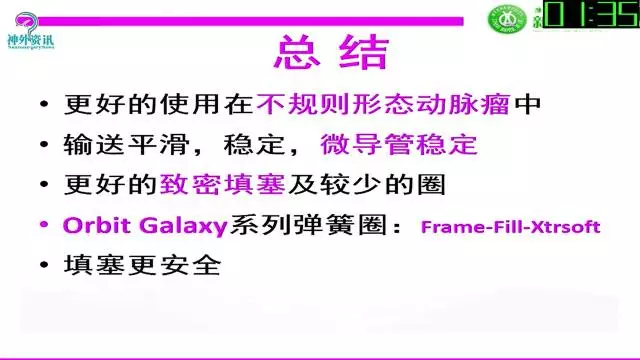

今天为大家分享的是“强生医疗CNV-神经介入专栏”第三十六期,由重庆第三军医大学附属新桥医院神经外科刘俊带来的“Galaxy弹簧圈在不规则动脉瘤中的临床应用”精彩讲课视频及PPT,欢迎观看。文章仅代表作者个人观点,如有不同见解,欢迎同道斧正!